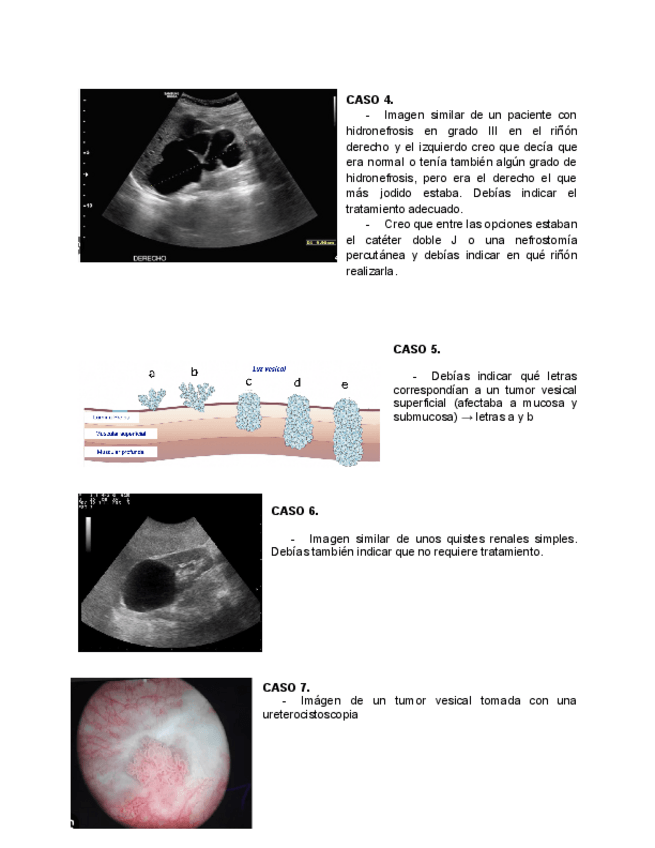

He publicado nuevos apuntes de 4º Nefrologia y Urología: Examen-practico-urologia-2025.pdf

3 páginas